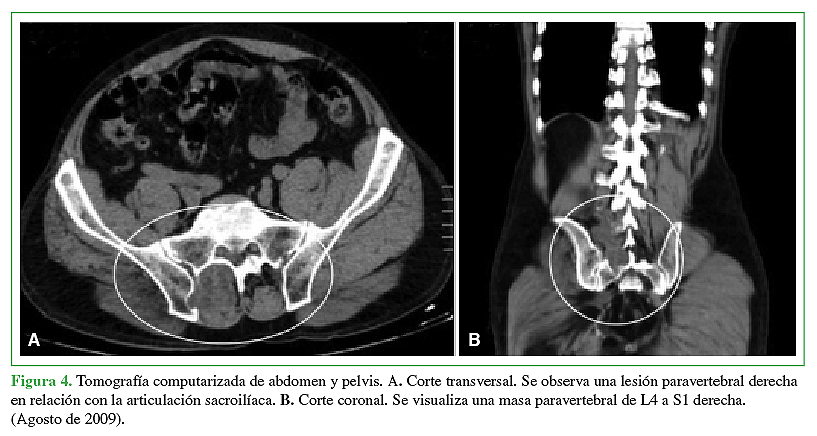

La hidatidosis es una enfermedad causada por el estado larval del platelminto Echinococcus, siendo la especie más prevalente Echinococcus granulosus. Es endémica Eurasia, Africa, Australia y Sudamérica. En Chile tiene una incidencia notificada de 2,1 casos por 100.000 habitantes y a pesar de que está asociada a las zonas ganaderas del sur de Chile, se presenta a lo largo de todo el territorio debido al desplazamiento de la población y su largo período de incubación. Se caracteriza por la presencia de un quiste habitualmente a nivel hepático (75%) o pulmonar (15%). La afectación de otros territorios es menos frecuente y el compromiso óseo es una rareza que no supera el 1 a 2,5%, ya sea en el tejido trabecular o canal medular. El tratamiento por lo general es médico-quirúrgico con resultados clínicos dispares debido a alta tasa de recurrencias y secuelas. La experiencia en el manejo de pacientes afectados con hidatidosis intrarraquídea es limitada debido a su baja frecuencia. Por ello quisimos reportar 2 casos observados en nuestro centro y analizar su manejo.Descargas